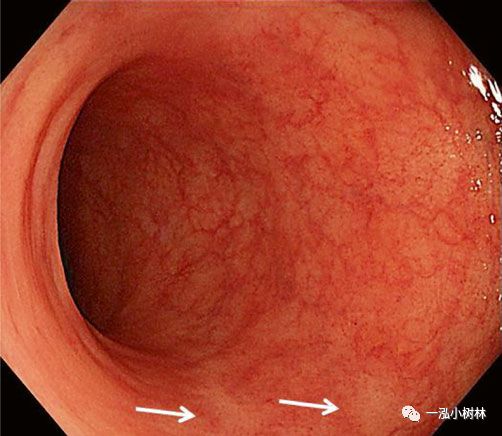

随着高清晰度白光内镜或高分辨率内镜(HRE)应用以来,增加了结肠息肉的检出率。高清白光内镜产生的图像分辨率更高(>100万像素)。HRE使内镜医生能够观察详细的黏膜和血管信息(图1)。在IBD患者中,可以详细观察到血管的形态,因此,内镜能够诊断缓解期UC患者病变。由于HRE在检测IBD高危人群的息肉和腺瘤方面有临床益处,它也被证明对发现IBD患者的结肠炎相关异型增生/癌是有用的(图2)。尽管靛胭脂染色的HRE对于发现结肠炎相关异型增生/癌是有用的,但NBI对异型增生的诊断准确性仍存在争议(参见NBI)。

图1 高清晰度内镜可以观察溃疡性结肠炎患者的详细黏膜炎症。即使处于缓解期,血管形态也不完全正常,也可观察到白色疤痕(箭头)。